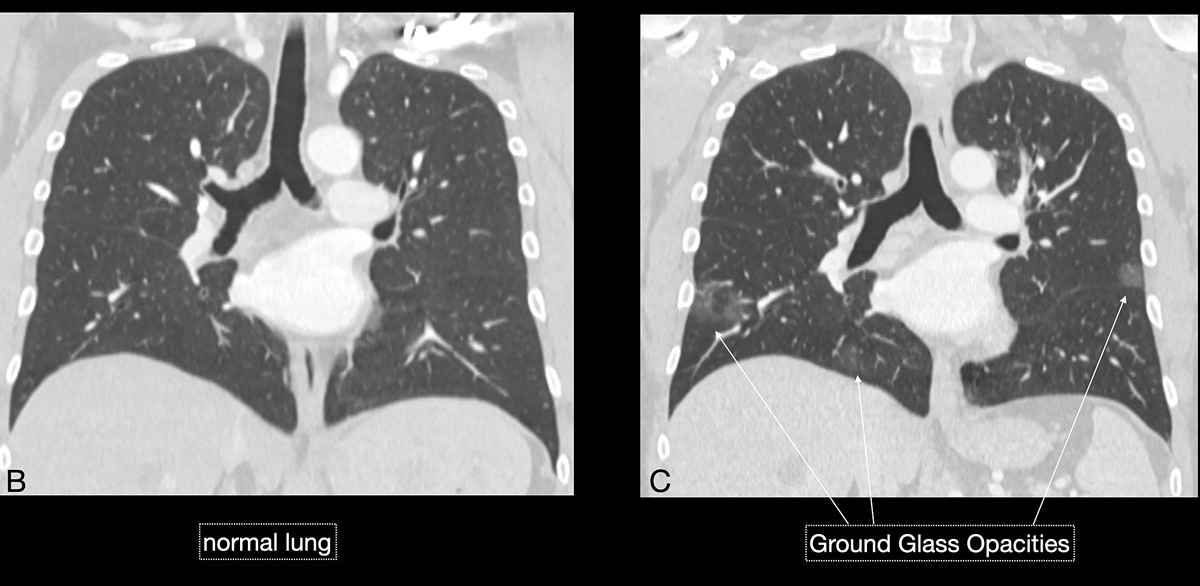

Imaging features in our patient cohort are summarised in table 2 and compared with manifestations observed on CT in Chinese patients [20]. Classic imaging findings are bilateral ground glass opacities with or without areas of consolidation, predominantly with a peripheral or basal lower lobe distribution (figs 3 and 5 ). Unilateral or bilateral ground glass opacities – the hallmark of an early infection (0–4 days) – were observed in almost all COVID-19 patients on chest CT examinations (97% positivity). Given the very subtle appearance of ground glass opacities, their detection on chest x-ray is difficult and often not made prospectively. The second most apparent imaging patterns are consolidations, which are typically multifocal, subpleural/peripheral, or in a peribronchovascular distribution (figs 3 and 5 ). As the disease progresses (5–8 days), the extent of ground glass opacities increases and the amount of consolidation rises (fig. 6). The ground glass opacities progressively transform into consolidative opacities featuring patterns of organising pneumonia of varying extents in the peak stage (10–13 days), before gradually resolving with the patient’s recovery. Typical patterns of organising pneumonia include subpleural lines/bands, perilobular thickening, arcade and atoll signs. Generally, the development of consolidations is a sign of disease progression and is more common in patients above 50 years old and those who have experienced a longer duration of symptoms.

Figure 6 BC A prior chest computed tomography (CT) (B) compared with the current chest CT (C) demonstrated development of small foci of bilateral ground glass opacities, supporting the clinical suspicion of COVID-19. Mini-bronchoalveolar lavage (BAL) was consequently performed and confirmed SARS-Cov-2 virus in BAL fluid.